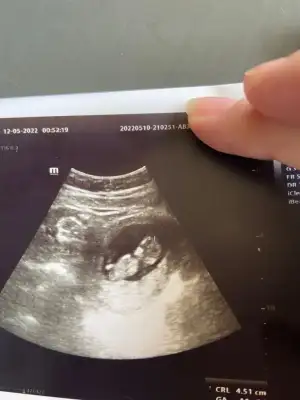

Hala kız gibi duruyor13 haftalık göstermedi bugün kendinidaha önce kız dedin hadi bakalım :)

başka foto yok mu burda göbekten aşağı görünmüyor, ayrıca renkli değil de siyah beyaz varsa? 7-8 haftalık hali de varsa onu da yüklerseniz yorum yapabilirimkarından 13 haftalık burda![]()

bu tek vardıbaşka foto yok mu burda göbekten aşağı görünmüyor, ayrıca renkli değil de siyah beyaz varsa? 7-8 haftalık hali de varsa onu da yüklerseniz yorum yapabilirim